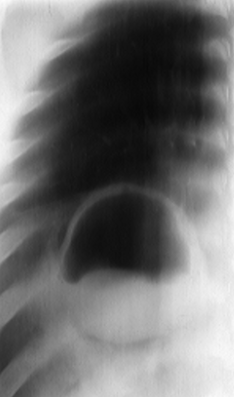

Rx toracică, incidență P-A

DESCRIERE:

Leziune hidro-aerica pulmonara cu nivel hidro-aeric convex (imagine in menisc) si perete subtire si neted

DX: chist hidatic evacuat

DD: